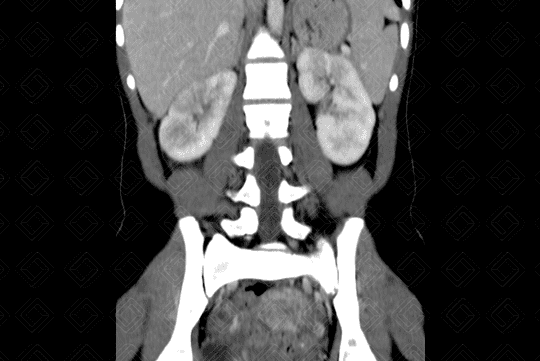

Descrição da lesão: Tomografia computadorizada após a administração do contraste venoso (imagens no plano axial - figuras 1 e 3; e plano coronal - figura 2). Observa-se realce heterogêneo do parênquima renal, com áreas hipocaptantes do meio de contraste venoso (aspecto conhecido como nefrograma estriado).

Há, ainda, lâmina líquida no espaço perirrenal direito (figura 1) e espessamento do urotélio à esquerda (figura 3 - seta vermelha). Estes aspectos são compatíveis com pielonefrite aguda.